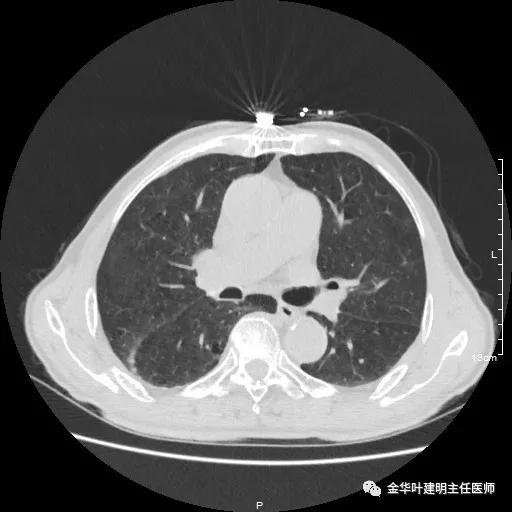

以上示右肺中叶病灶3。是混合磨玻璃结节,位置差,邻近肺门部,无法局部楔形切除,抗炎治疗后靶扫描显示了更清楚的细节,是典型的肺癌影像特征(此处未另提供)。从单病灶来看,需要行右肺中叶切除并清扫淋巴结才能得以治疗。

以上示右中叶病灶4。也是囊腔型病灶,病灶大,囊壁是磨玻璃密度,亦是较为典型的囊腔型肺癌影像。单病灶看,需中叶切除来治疗,因病灶3的存在,中叶切除可同时解决病灶3与病灶4。